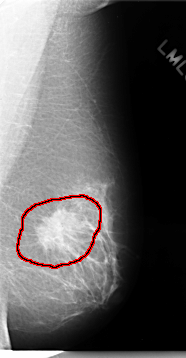

C_0075_1.LEFT_MLO

FILE: C_0075_1.LEFT_MLO.OVERLAY

TOTAL_ABNORMALITIES 1

ABNORMALITY 1

LESION_TYPE MASS SHAPE IRREGULAR MARGINS SPICULATED

ASSESSMENT 5

SUBTLETY 5

PATHOLOGY MALIGNANT

TOTAL_OUTLINES 1

BOUNDARY